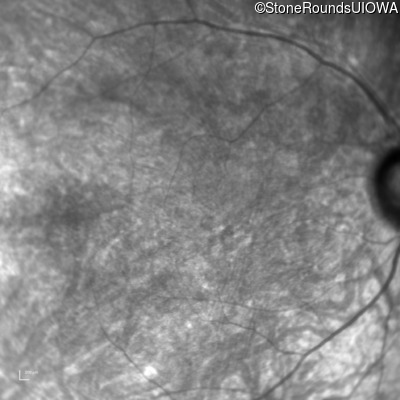

Infrared Fundus Photograph - Left - 20/100 -2 sc

Exemplar